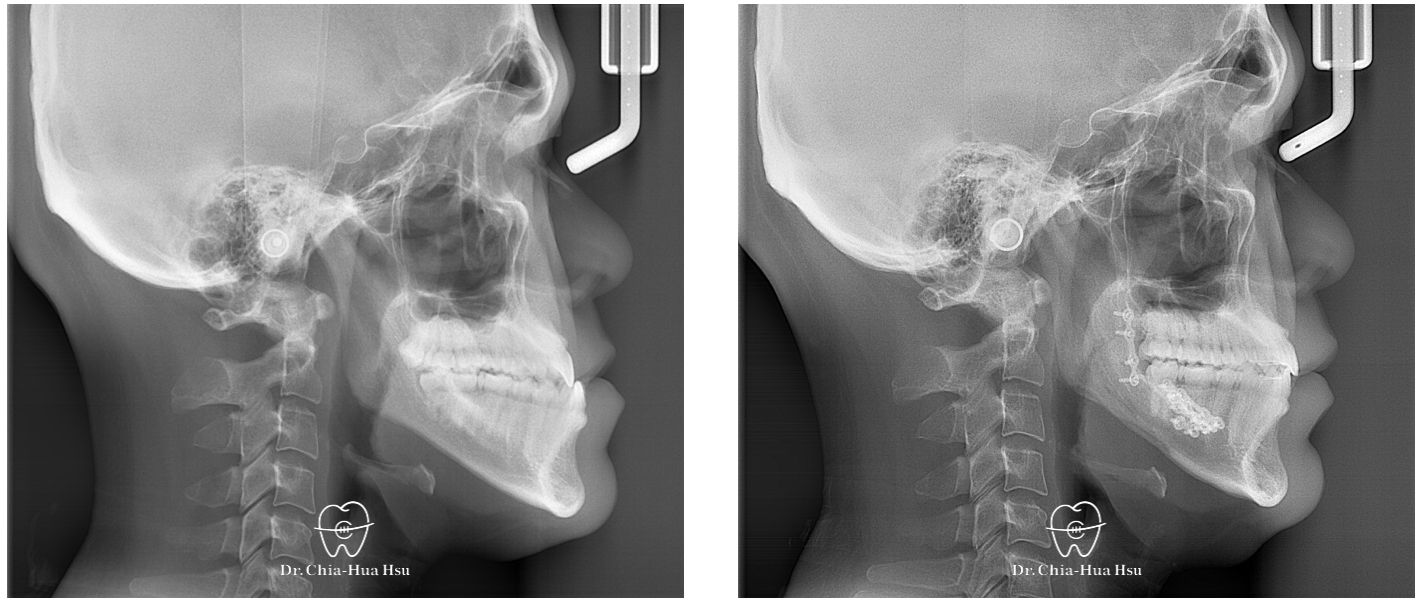

手術前使用軟體模擬骨塊移動路徑,以方便手術中定位。

治療前

治療後

治療前

治療後